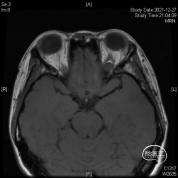

头颅MR体检偶然发现左侧眶尖占位,初步诊断海绵状血管瘤,查体无明显阳性体征。

该部位的手术可选多种入路,经眉弓锁孔、经额、经眶外侧壁等,然而施炜、陈建内镜团队选择了临床较少使用的经眶入路!创伤小且对患者的容貌影响小,术前团队进行了相关解剖研究!

研究表明此入路除细小的滋养血管外无其他重要结构!皮肤切口选择近眶缘眉弓美容切口,紧贴眶上壁分离骨膜,保护眶筋膜,病变紧贴眶上壁,导航下确定眶尖紧贴眶上壁的病变,外观呈浅紫兰色,考虑既往有出血所致,显露肿瘤!

磨除局部少许隆起的骨嵴以增加操作空间,切开眶骨膜分离并完整切除病变,术中证实为海绵状血管瘤,直径约1厘米,手术全程在内镜下完成。